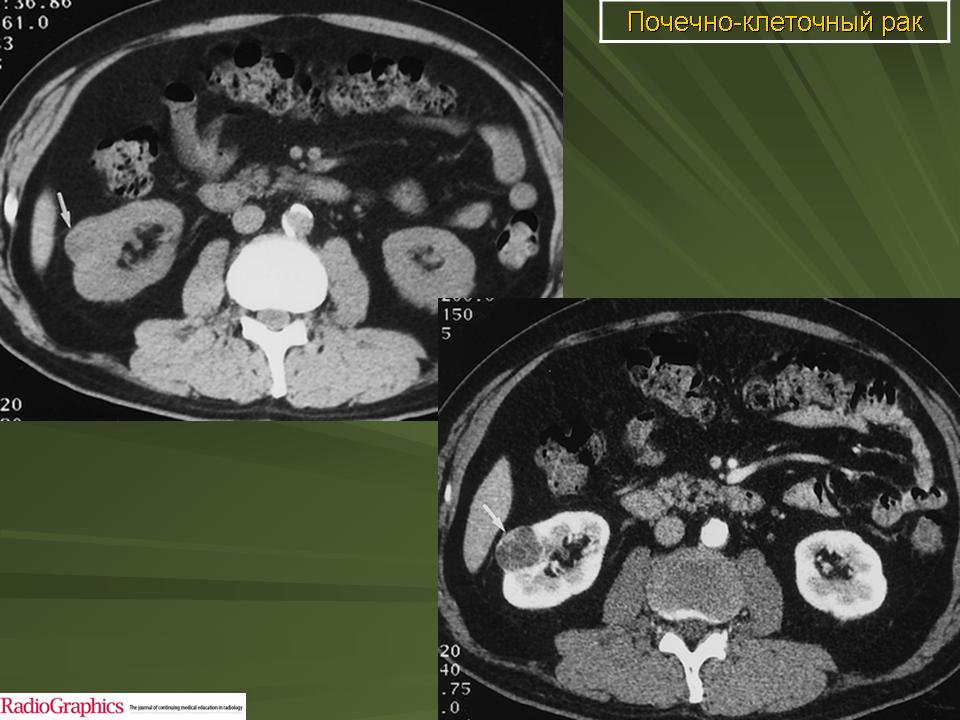

Укажите метод исследования и интерпретируйте полученные данные// +КТ - Новообразование правой почки// КТ - Киста правой почки// МРТ - подкапсульная гематома правой почки// МРТ – аномалия развития правой почки// МРТ - Новообразование правой почки

Какой вид исследования почек вы видите// УЗИ брюшной полости// зкскреторная урография// МРТ брюшной полости// +КТ брюшной полости// Сонография